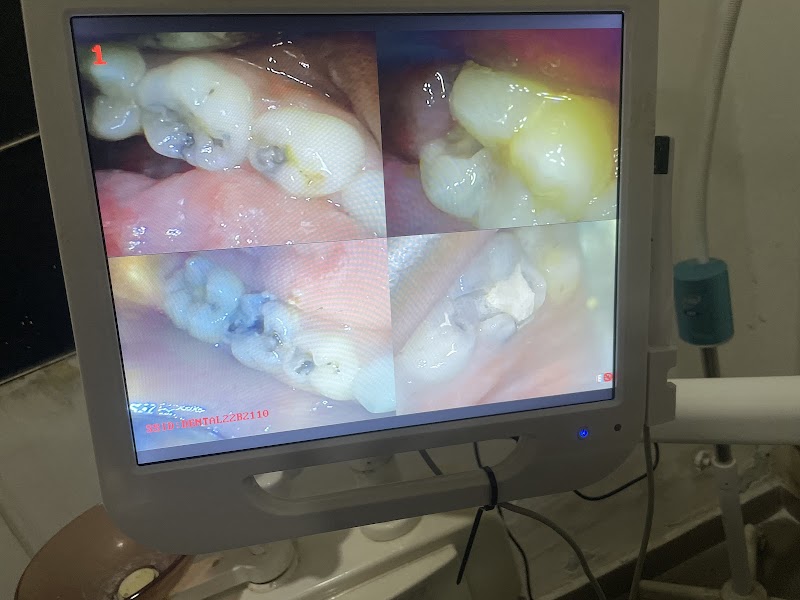

Présentation

Photos